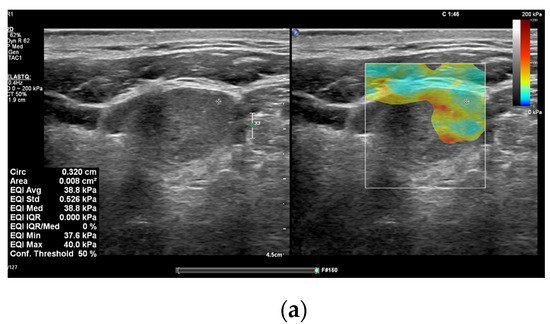

In recent years, many research papers have demonstrated that multiparametric evaluation of focal thyroid lesions using conventional US in association with elastography and CEUS enhances the sensitivity and specificity of ultrasound in predicting thyroid malignancy (Figure 1 and Figure 2).

Figure 2.

A 52 years old male with multifocal papillary thyroid carcinoma developed on multinodular goiter. (a) Quantitative shear wave elastography (SWE) revealed 38.8 kPa; (b) qualitative contrast-enhanced ultrasound (CEUS) of the nodule revealed heterogenous hypo-enhancement and quantitative CEUS revealed a time to peak of 10.07 s and a peak intensity of 3.18 dB.